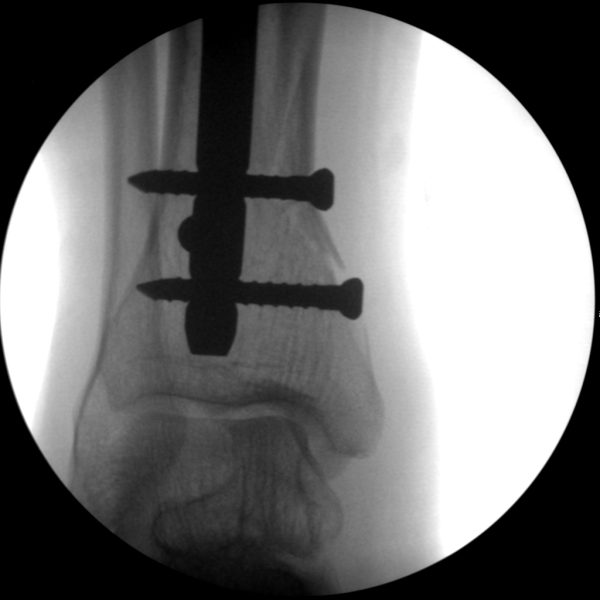

CRIF - Closed reduction internal fixation

ORIF - Open reduction internal fixation

Skan-C is a great C-arm for orthopaedic treatments for several reasons